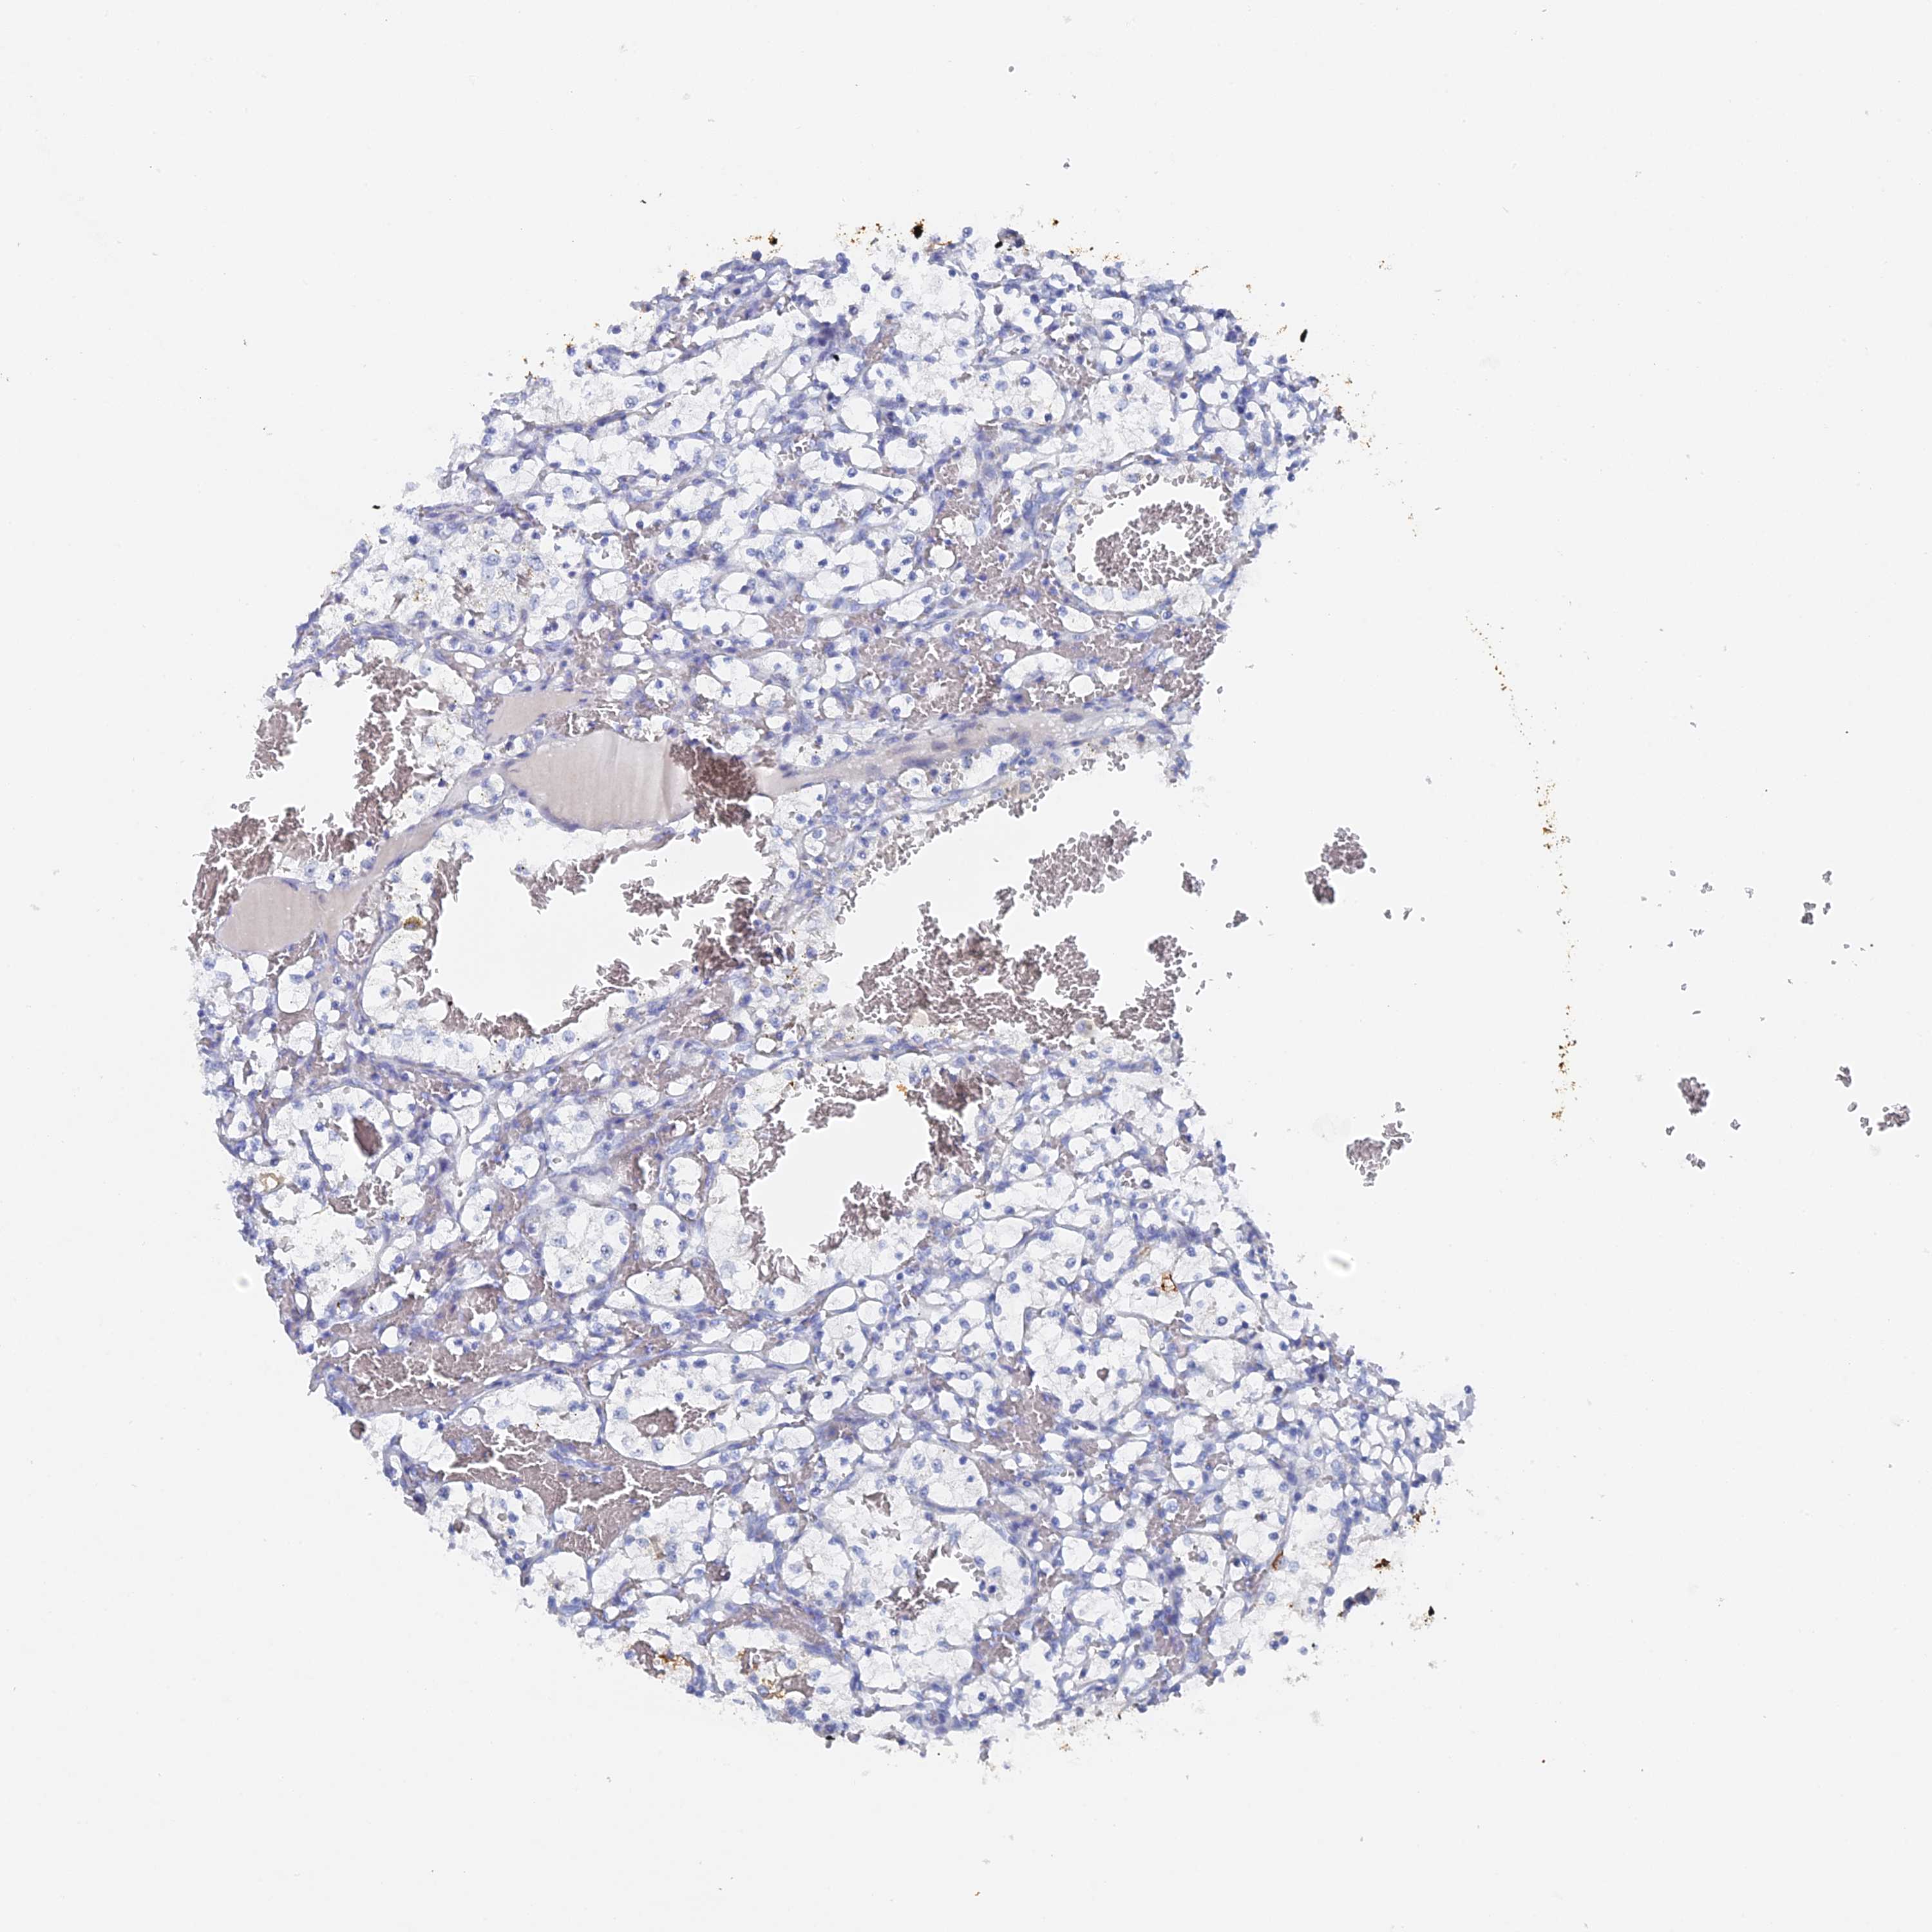

KIDNEY RENAL CLEAR CELL CARCINOMA (VALIDATION) - Interactive survival scatter ploti

The Survival Scatter plot shows the clinical status (i.e. dead or alive) for all individuals in the patient cohort, based on the same data that underlies the corresponding Kaplan-Meier plots. Patients that are alive at last time for follow-up are shown in blue and patients who have died during the study are shown in red.

The x-axis shows the expression levels (FPKM) of the investigated gene in the tumor tissue at the time of diagnosis. The y-axis shows the follow-up time after diagnosis (years). Both axes are complimented with kernel density curves demonstrating the data density over the axes. The top density plot shows the expression levels (FPKM) distribution among dead (red) and alive patients (blue). The right density plot shows the data density of the survived years of dead patients with high and low expression levels respectively, stratified using the cutoff indicated by the vertical dashed line through the Survival Scatter plot. This cutoff is automatically defined based on the FPKM cutoff that minimizes the p-score. The cutoff can be changed by dragging the vertical line or by entering a cutoff value in the square labeled "Current cut-off".

Under the Survival Scatter plot the p-score landscape (black curve; left axis) is shown together with dead median separation (red curve; right axis). Dead median separation is the difference in median mRNA expression between patients who have died with high and low expression, respectively. It is calculated as follows: median FPKM expression of dead patients with high expression - median FPKM expression of dead patients with low expression. This is intended to aid the user in visually exploring custom cutoffs and the associated p-scores and dead median separation.

Individual patient data is displayed and can be filtered by clicking on one or more of the category buttons on the top of the page. Categories describing expression level and patient information include: high, low, alive, dead, female, male and tumor stages. The scale of the x-axis can be toggled between linear and log-scale by clicking on the "x log" button. Mouse-over function shows TCGA ID, patient information and mRNA expression (FPKM) for each patient.

& Survival analysisi

Kaplan-Meier plots summarize results from analysis of correlation between mRNA expression level and patient survival. Patients were divided based on level of expression into one of the two groups "low" (under cut off) or "high" (over cut off). X-axis shows time for survival (years) and y-axis shows the probability of survival, where 1.0 corresponds to 100 percent.

SRFBP1 is not prognostic in Kidney Renal Clear Cell Carcinoma (validation)

Best expression cut offi

Based on the FPKM value of each gene, patients were classified into two groups and association between prognosis (survival) and gene expression (FPKM) was examined. The best expression cut-off refers the FPKM value that yields maximal difference with regard to survival between the two groups at the lowest log-rank P-value. Best expression cut-off was selected based on survival analysis .

When clicking on this number, the vertical dashed line indicating cut-off, the interactive survival plot, and the Kaplan-Meier curve will be adjusted to show results based on the best expression cut-off.

: 12.21

P scorei

Log-rank P value for Kaplan-Meier plot showing results from analysis of correlation between mRNA expression level and patient survival.

N/A

TCGA RNA samplesi

RNA-seq data is reported as average FPKM (number Fragments Per Kilobase of exon per Million reads), generated by the The Cancer Genome Atlas (TCGA) .

Normal distribution across the dataset is visualized with box plots, shown as median and 25th and 75th percentiles. Points are displayed as outliers if they are above or below 1.5 times the interquartile range. FPKM values of the individual samples are presented next to the box plot.

Average pTPM 10.5

Number of samples 100